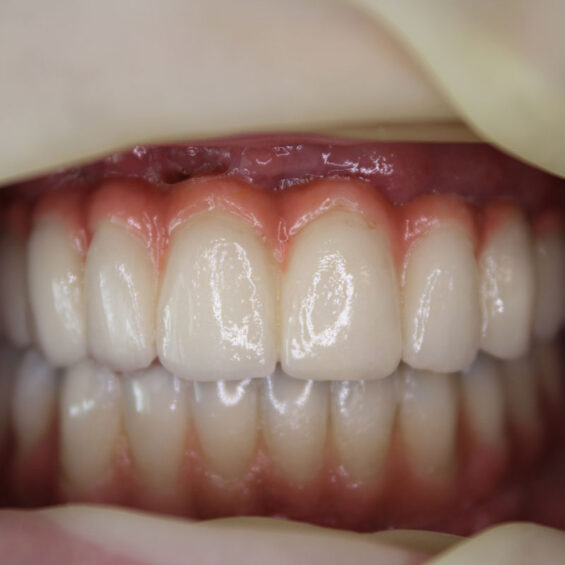

Decidí acudir ya que no aguantaba el dolor que tenía, no podía comer y me afectaba en el día a día. Cuando Susana me exploró, inmediatamente supo lo que necesitaba. Los dientes que me quedaban no podían aguantar más tratamientos Planificó la extracción de todos ellos y el tratamiento de All On Four superior y 6 implantes mandibulares . Con colocación inmediata de dientes el mismo día que me los extrajo y colocó los implantes. Entrar y salir con dientes.

Valentín ha sido en todo momento un paciente comprensivo y colaborador. Su cirugía requirió una planificación muy precisa, pues se trataba de implantes postextracción y carga inmediata. Finalmente, una rehabilitación fija sobre implantes con todos los criterios que exigía.

- Rehabilitación completa sobre implantes